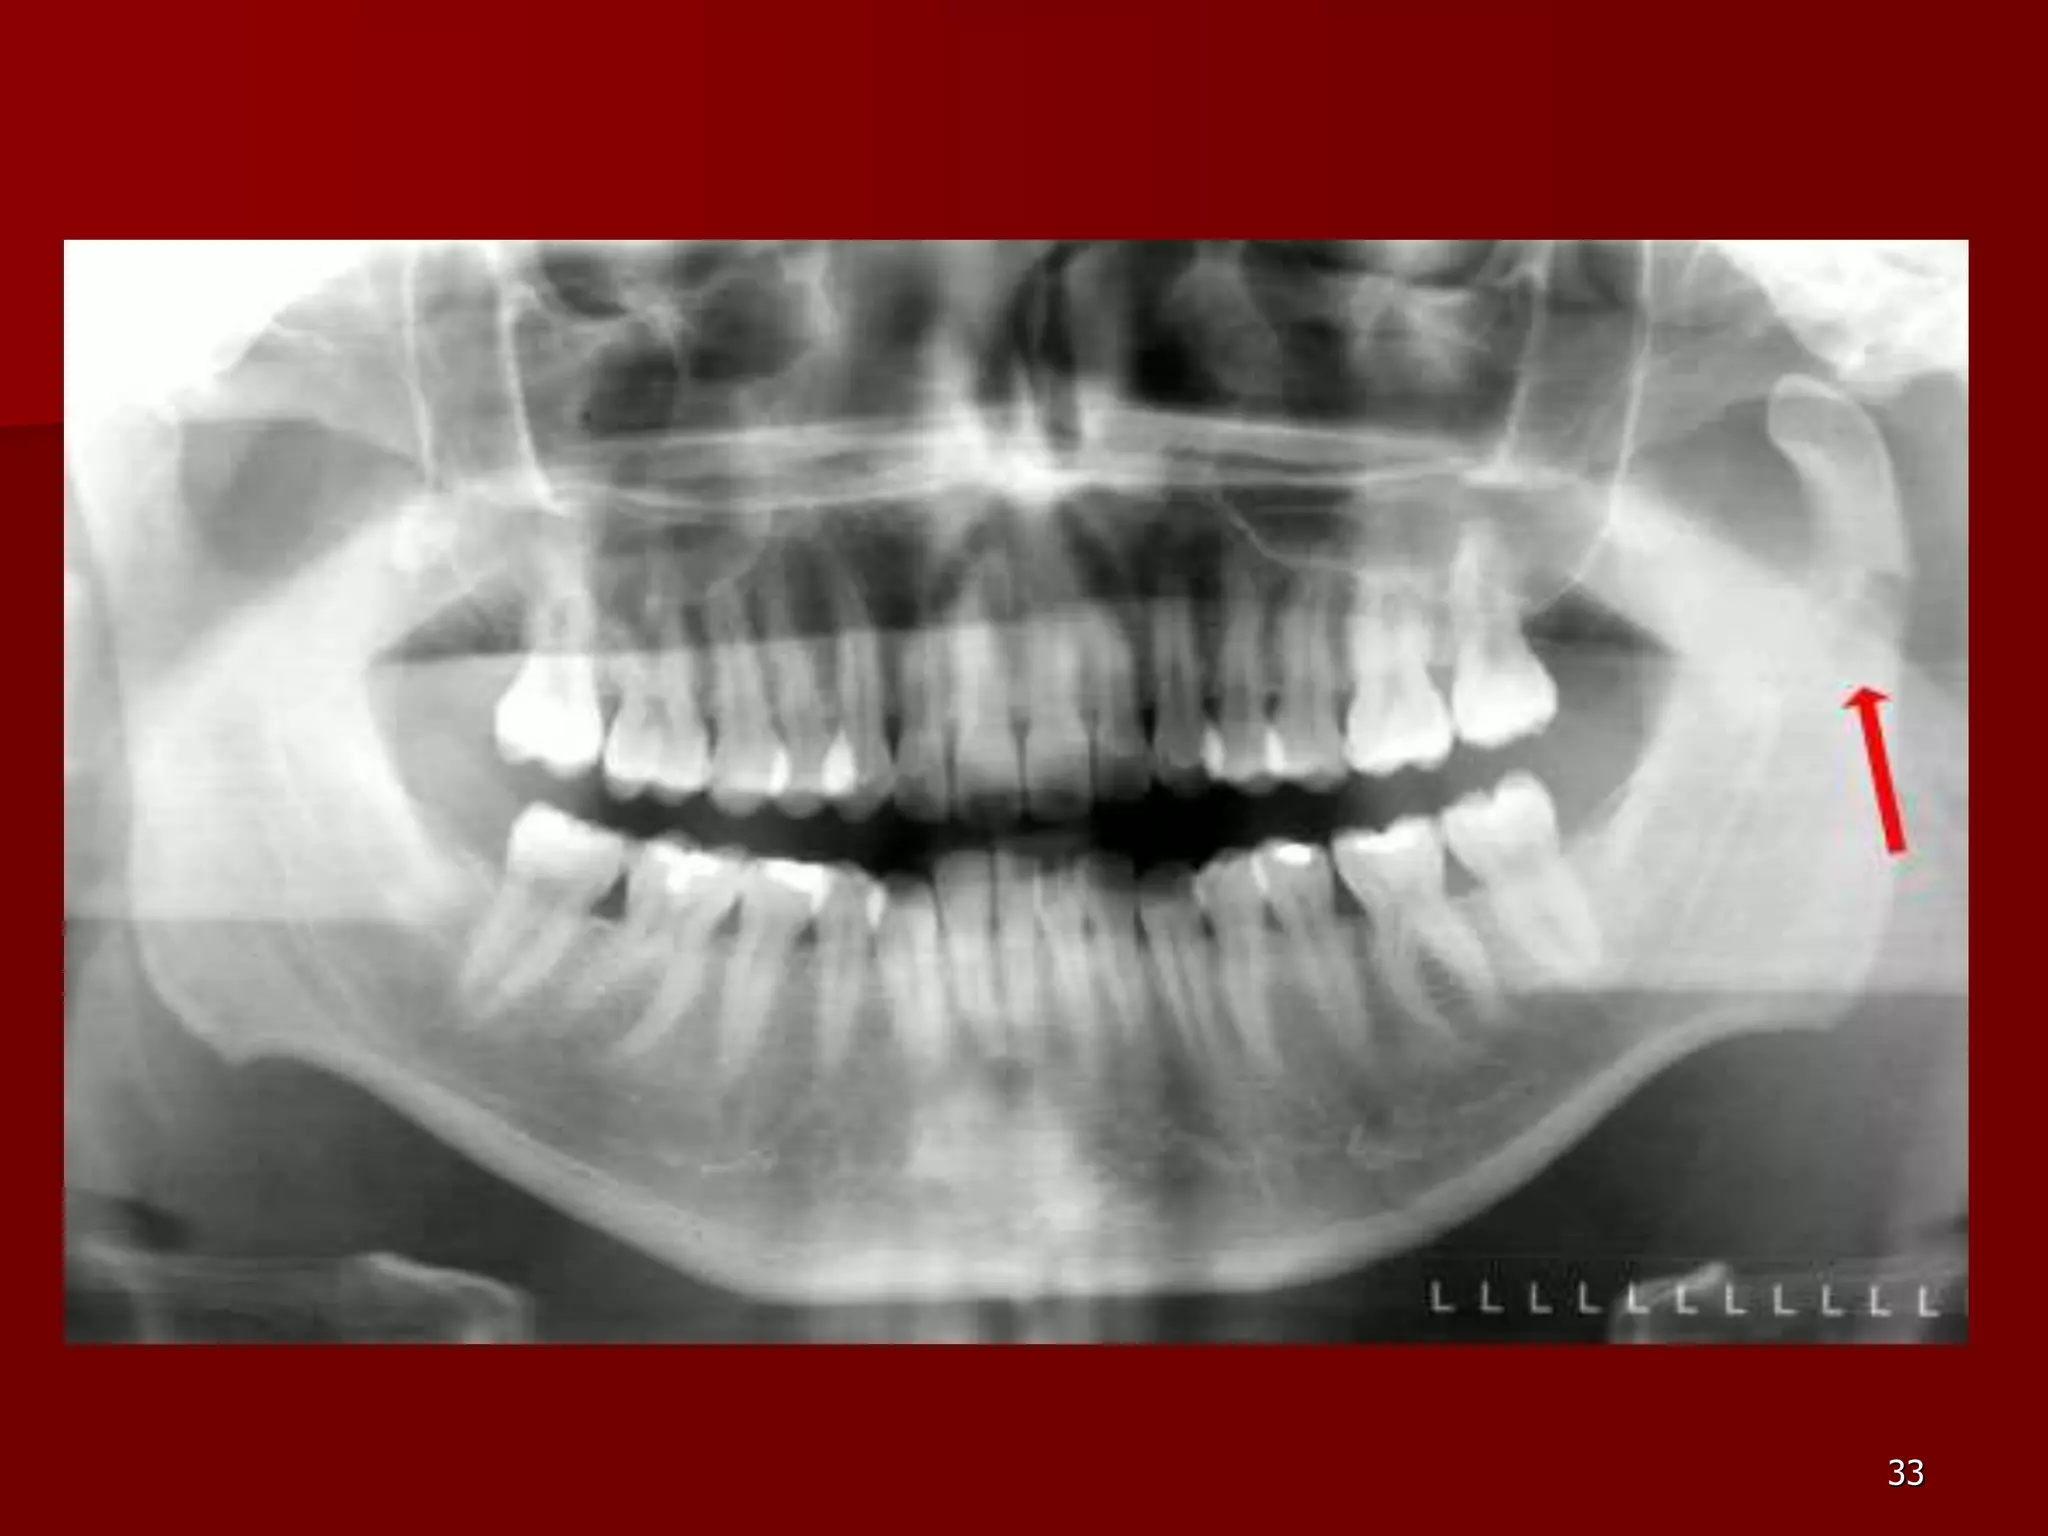

Fracturile condiliene.

 b. fractura subcondiliana inalta –

traiectul este la nivelul 1/3 medie a

gatului condilului mandibular, de

regula fiind orizontal. Deplasarea

implica basculare sau luxatie catre

interior si inainte sub actiunea

tendonului muschiului pterigonian

extern. 32